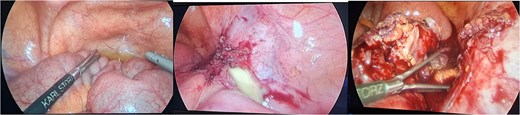

Histopathology examination of our rare case confirmed the diagnosis of acute appendicitis. Gross examination, the mesenteric mass (6 cm) (Fig. 7). Microscopically, it displayed a mixed lymphoplasmacytic infiltration, hyalinized arteries that resembled ‘lollipops,’ and an enlarged lymph node with retrograde follicles. Immunostains revealed polytypic plasma cells, CD20+ B cells, a few CD10+ germinal centers, CD3+/CD5+/CD8+ T cells, a disturbed CD21/CD23 meshwork, and CD31+/CD34+ endothelium. HHV8 stain is negative, and Epstein-Barr virus (EBV) stain showed rare positive cells consistent with past infection (Fig. 8). Serology for HHV8 and HIV is negative.

Gross examination (a, b): Mesenteric oval mass (6 cm) with gray homogenous cut surface.